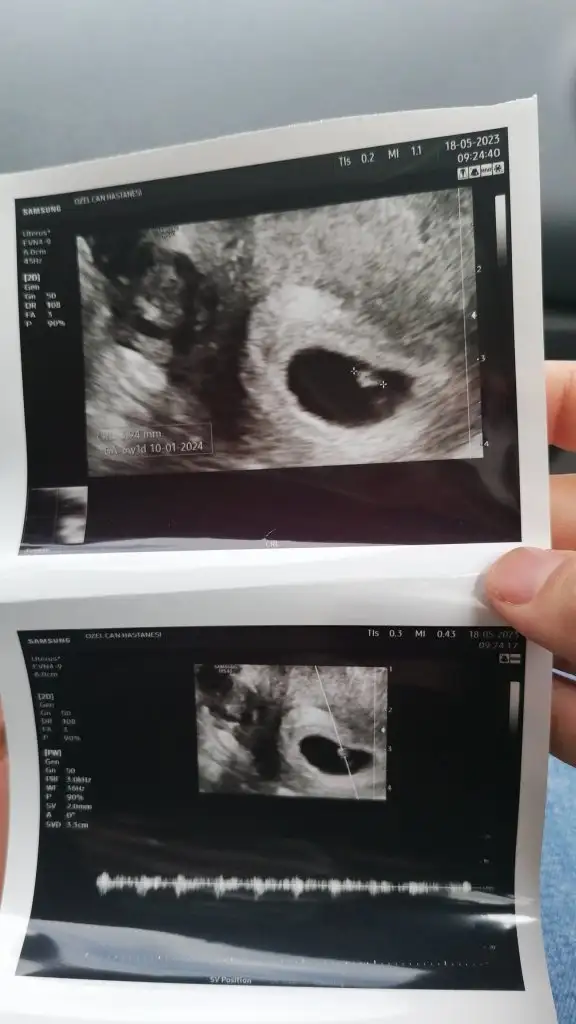

Selamlarr🌼öncelikle inşallah sağlıkla kucağımıza alırız bebişlerimizi🙏🏻 biz bugün 6+6olduk dr kontrolumuz vardı, karından ultrosonla bebişi gördük😻kalp atışını da gördük ama tam duyulmadıği için vajinal baktı ve minik minik duyduk Allah isteyen herkese nasip etsin çok farklı duygularmış 🥺 Dr herşey yolunda haftasıyla uyumlu dedi ama ultrosonda 6+1 yazıyor sanırım rica etsem anlayan bi bakabilir mi

Eklentiler

• IMG-20230518-WA0002.webp

IMG-20230518-WA0002.webp

23,7 KB · Görüntüleme: 90